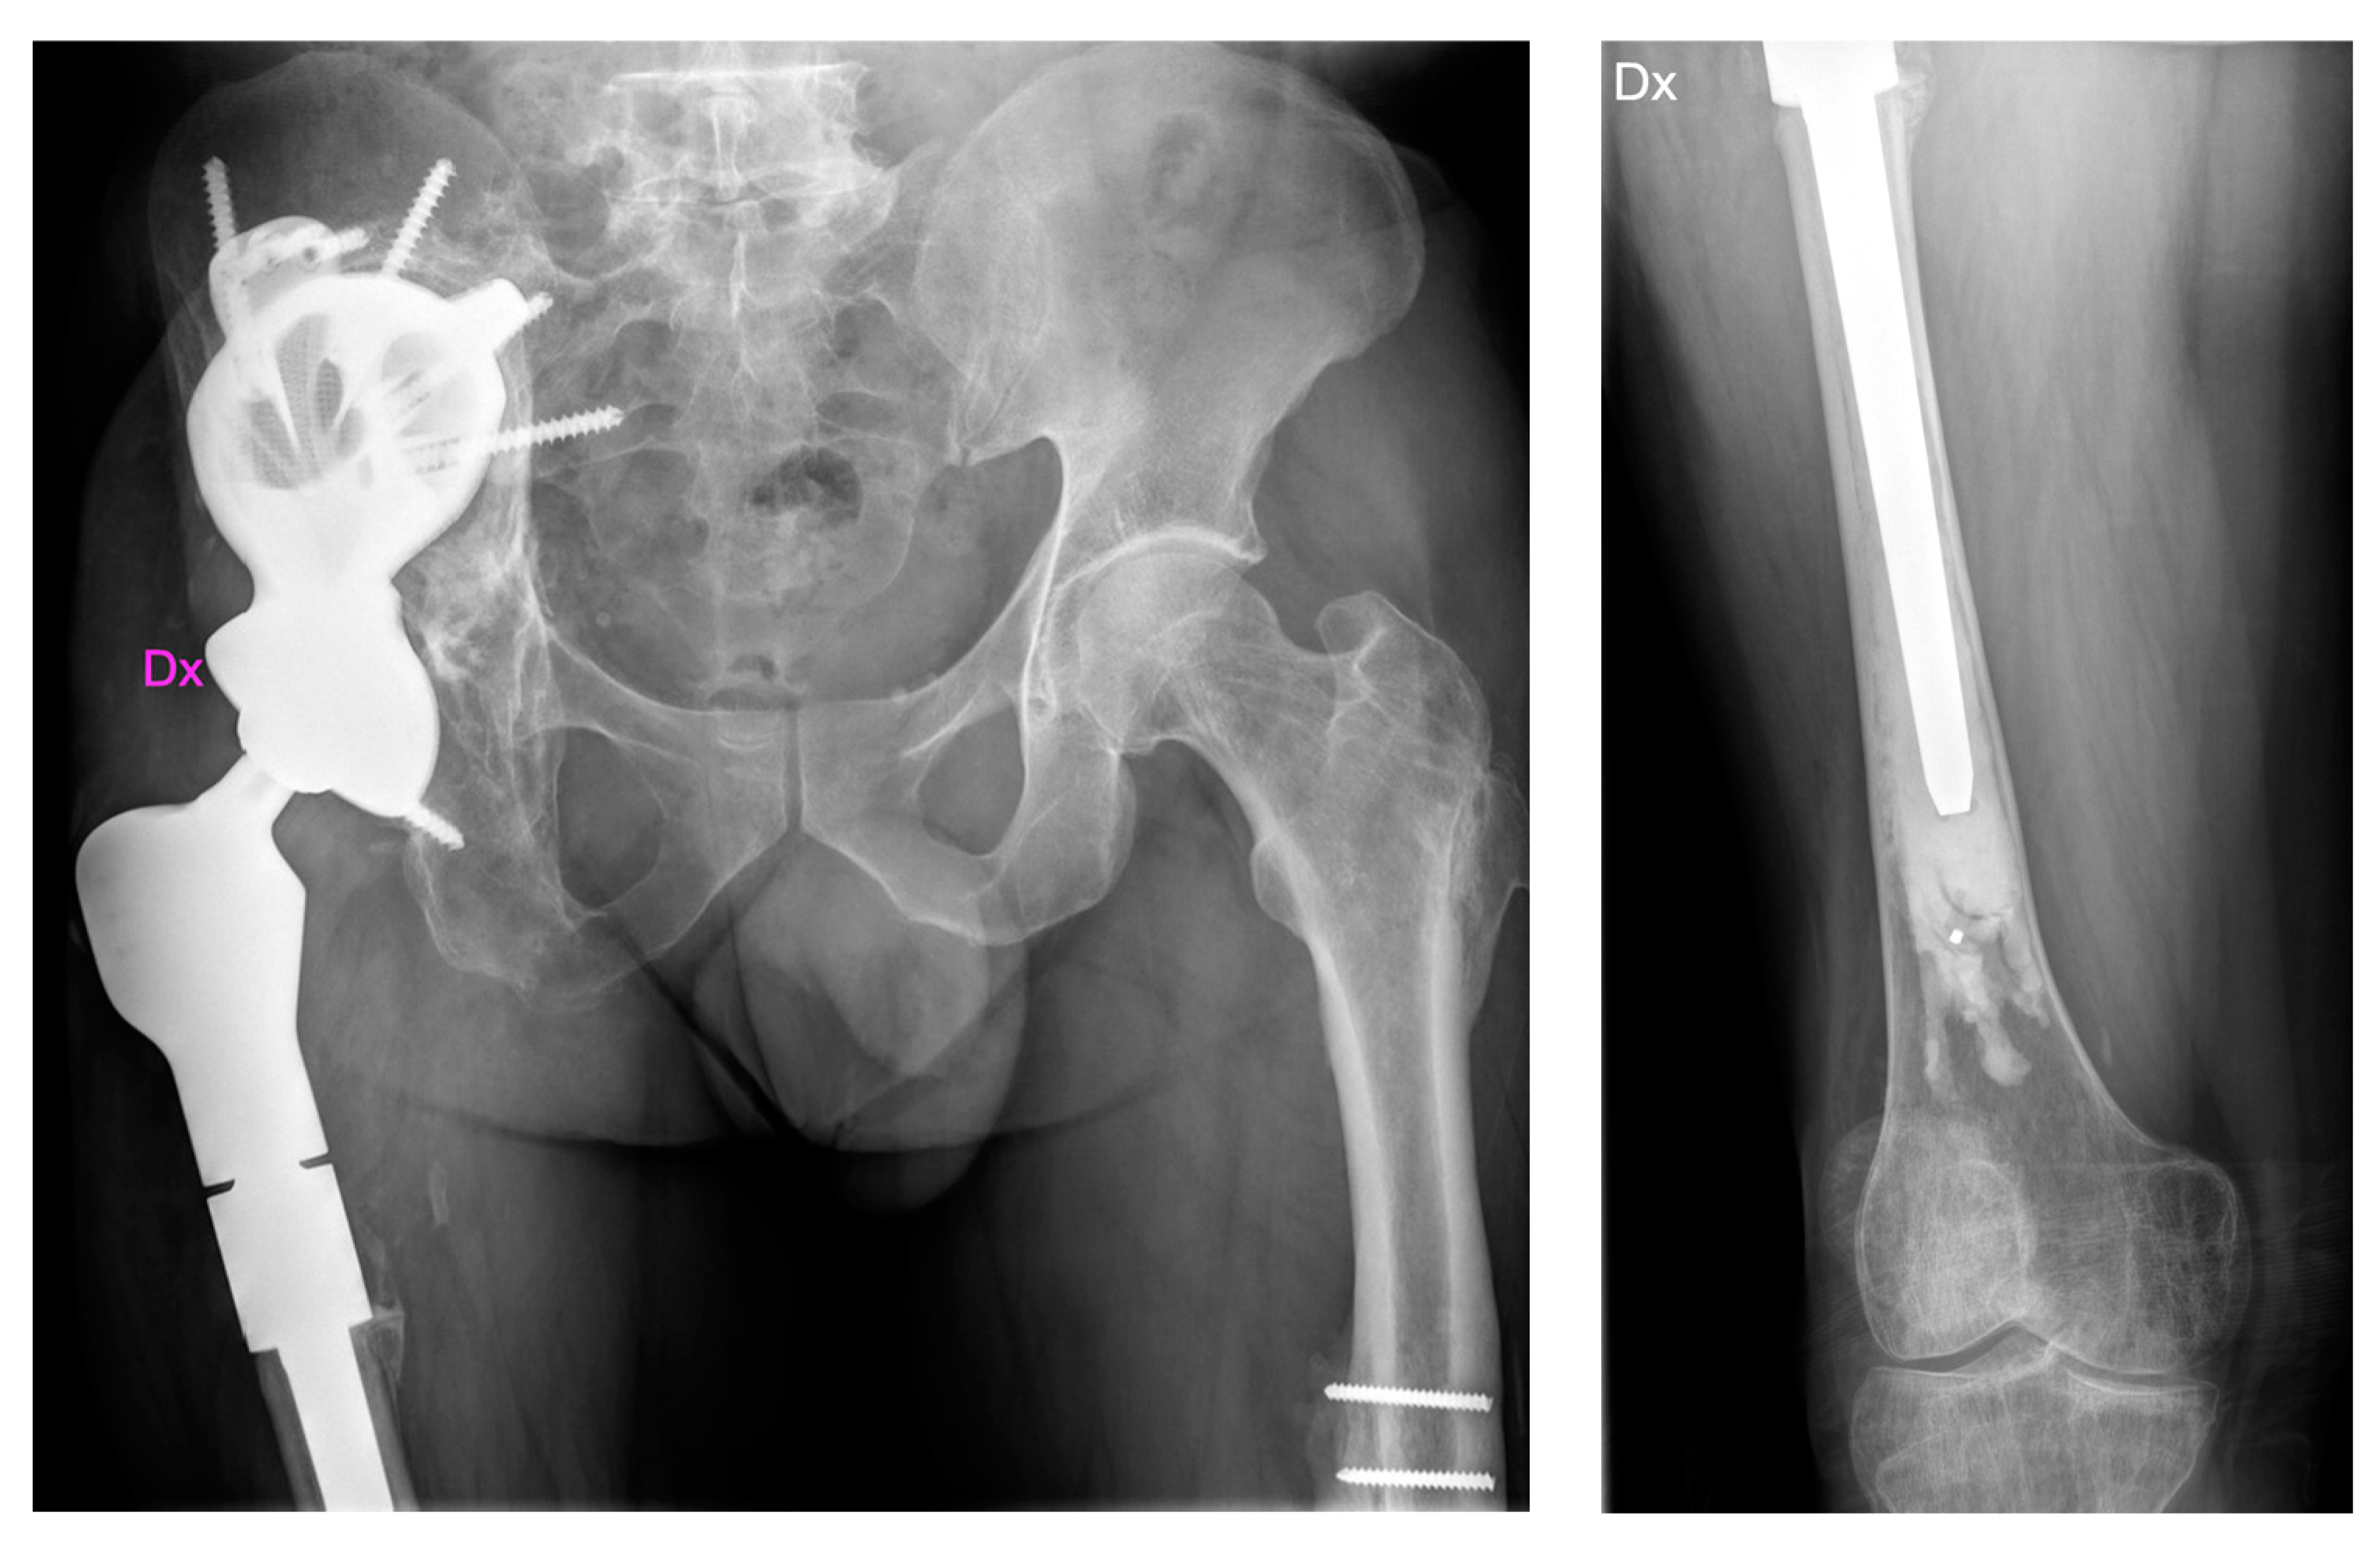

2.1. Case #1

2.2. Case #2